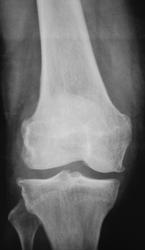

С диагнозом ДОА, пациент направлен на рентгенографю коленного сустава.

Деформирующий артроз. Есть признаки обызвествления мест прикрепления крестообразных связок, собственной связки надколенника.

ДОА коленного 2 ст. и надколенно-большеберцового сустава 3-4 стадий (по Larsen)..